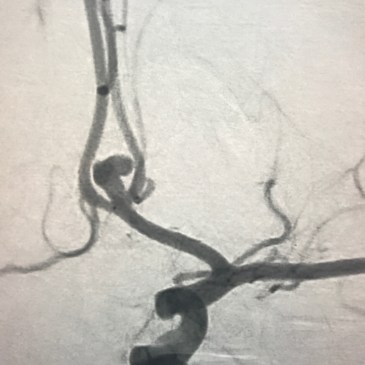

The Myth That Small Brain Aneurysms Don’t Rupture

This week, the Annals of Internal Medicine published this systematic review , where the authors concluded that small aneurysms (7mm or less) have low annualized risk of rupture, despite reviewing a collection of poor quality data for the analysis. It’s studies like this, based on poor quality data, that propagate false conclusions for the public and … More The Myth That Small Brain Aneurysms Don’t Rupture